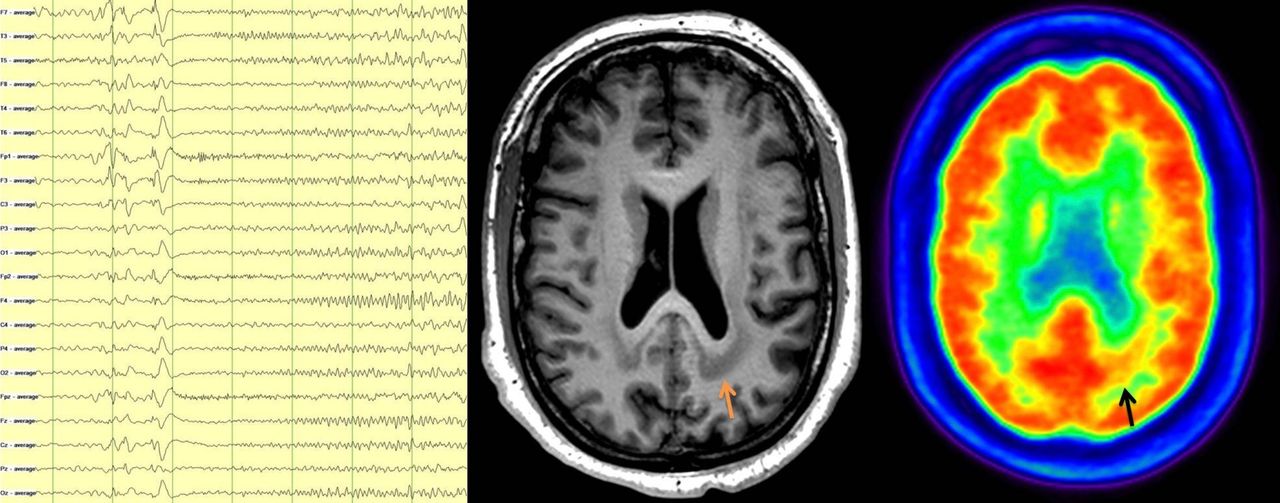

Neurólogo especializado en Epilepsia en todas las edades, tanto en edad pediátrica como en adultos. Director del Departamento de Neurociencias Clínicas del Hospital Blua Sanitas Valdebebas, Madrid, y de la Unidad de Epilepsia de este grupo, un equipo multidisciplinar único en sus características en España. Consulta y unidad de diagnóstico y tratamiento de epilepsia compleja en Madrid. También posibilidad de vídeoconsulta online. Especialista en crisis funcionales, las antiguamente conocidas como pseudocrisis, crisis psicógenas no epilépticas o conversivas, con el primer equipo multidisciplinar para su cuidado en España. Consulta y genética privada con ingresos, urgencias y pruebas de la máxima calidad cubiertas por seguros (vídeo-EEG prolongado, resonancia cerebral 3T). Visión multidisciplinar, estimulación, neurodesarrollo, neuropsicología, neuronutrición y conducta. Cirugía de epilepsia con técnicas mínimamente invasivas. Nuevos ensayos clínicos con terapias de precisión. Unidad de crisis funcionales (psicógenas no epilépticas o disociativas), la única multidisciplinar en España. Segundas opiniones, seguimiento estrecho multidisciplinar y evaluación de pruebas complementarias: neuroimagen (resonancia magnética de alta definición, PET, magneto-EG, resonancia funcional), estudios neurofisiológicos (vídeo-electroencefalografía prolongada) o genéticos (panel de genes, array-CGH, exoma, genoma), metabólicos e inmunológicos (neuroinmunología en LCR y sangre), así como de valoraciones cognitivas y de neurodesarrollo para evitar efectos adversos de fármacos y de impacto en la calidad de vida más allá de las crisis epilépticas.